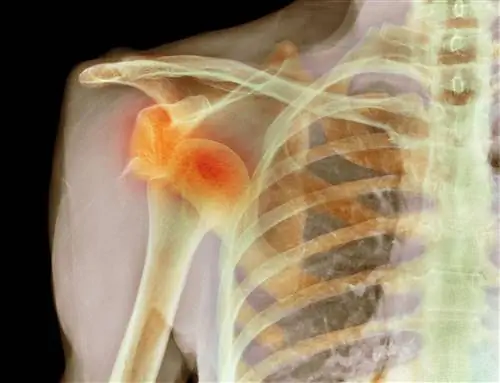

Переломы костей

Перелом ключицы, рентген

Перелом - это перелом кости, который может возникнуть либо в результате быстрого однократного повреждения кости (острый перелом), либо в результате повторяющейся нагрузки на кость с течением времени (стрессовый перелом).

Закрытые и открытые переломы

Закрытые переломы могут быть простыми (чистый перелом с небольшим повреждением окружающих тканей) или открытыми (перелом, при котором кость протыкает кожу с небольшим повреждением окружающих тканей). Большинство открытых переломов являются неотложными. Тот, который повреждает кожу, особенно опасен, потому что высок риск заражения.

Стрессовые переломы

Стрессовые переломы возникают в основном в стопах и голенях и часто встречаются в видах спорта, требующих повторяющихся нагрузок, в первую очередь в беговых/прыжковых видах спорта, таких как гимнастика или легкая атлетика. Бег создает на нижних конечностях силы, в два-три раза превышающие массу тела человека. Наиболее распространенным симптомом стрессового перелома является боль в этом месте, которая усиливается при физической нагрузке. Болезненность и припухлость часто сопровождают боль.